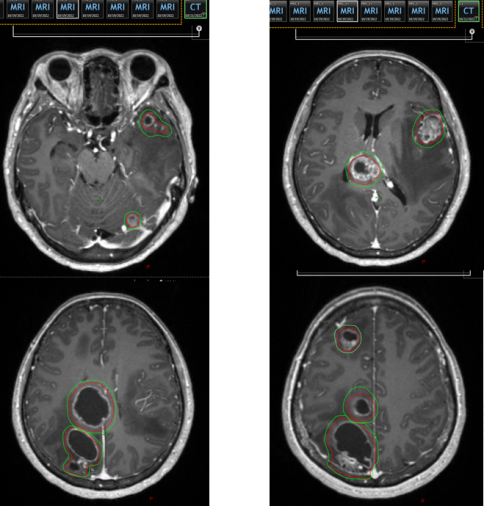

2.png

放疗靶区勾画示意图

采用国际领先的立体定向放疗设备——超弧刀HyperArc技术,精准覆盖了双侧小脑半球及各脑叶的转移灶,在给予肿瘤细胞毁灭性打击的同时,通过精确的剂量调控,将脑干、视交叉等关键正常组织的受照剂量严格控制在安全范围内,最大程度保护了神经功能。

考虑到颅内多发转移瘤已引发明显的压迫症状,若不及时控制,将严重威胁生命。聂大红教授果断决定,首先以精准放疗为“急先锋”,直击颅内病灶。